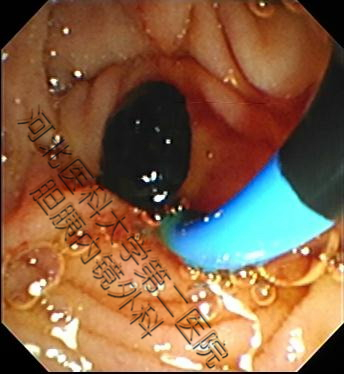

经十二指肠镜(ERCP)取石目前是治疗胆总管结石的首选方法。像做胃镜一样,将电子十二指肠镜从口腔插入,通过食管、胃、十二指肠到达十二指肠乳头部(胆胰管向十二指肠开口)后,先造影以便准确诊断,然后进行乳头括约肌的切开或者扩张,再行取石网篮直视下取石,腹部无切口、效果立竿见影!